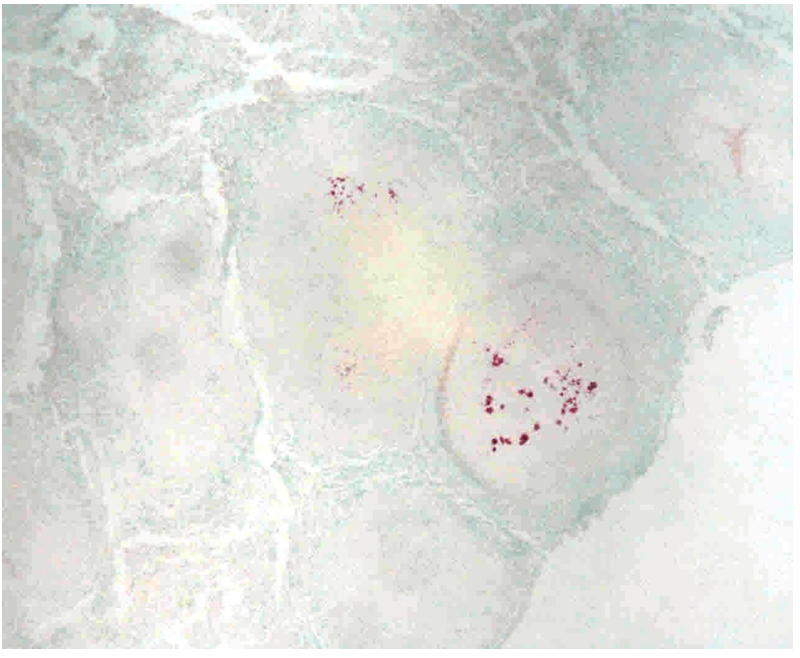

Pneumonia TBC miliaris- poultry (ZN) same as nr. 263

Ziehl-Nielsen staining is used for special proof of mycobacterium. Positive acid-fast rods bacilli and their clumps of red color are mainly found in the necrotic center. During the generalized TBC process, the lungs are the last organ with dissemination of tubercles.